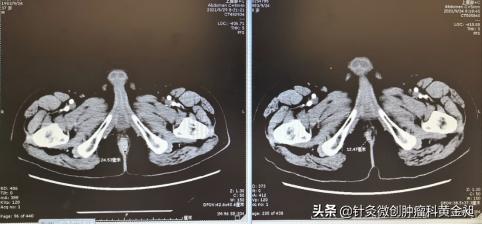

肛门区肿物2.4cm→1.2cm(左: 6月29日;右:9月24日)

会阴区肿物5.1cm*3.9cm→3.9cm*2.9cm(左: 6月29日;右:9月24日)